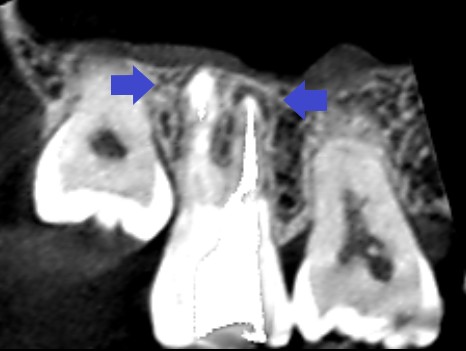

初診時の矢状断のCT画像です。

赤い矢印の先に黒い膿の影がみられ、膿は大きく埋伏している第三大臼歯(親知らず)に達しています。